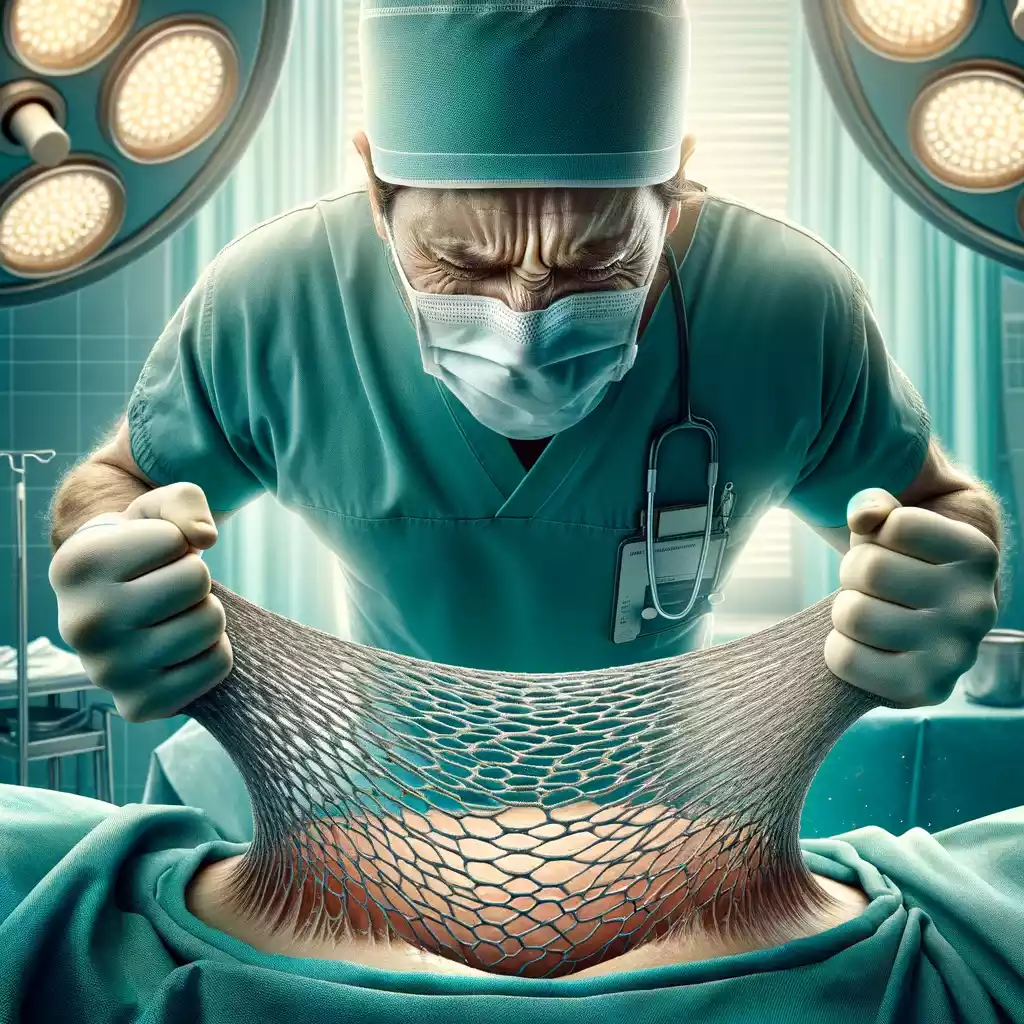

ZERWANIE SIATKI PO OPERACJI PRZEPUKLINY PACHWINOWEJ?

Siatka chirurgiczna jest stosowana w chirurgii przepukliny jako wsparcie dla mięśni i powięzi brzucha, aby aby nie powstał nawrót przepukliny. Siatka jest wkładana głęboko pod skórę pacjenta i jest przymocowana do tkanek brzucha, aby stanowić rusztowanie dla tkanek brzucha. Wiele osób pyta o rozerwanie siatki po operacji. Z jednej strony sama siatka jest silna. Z drugiej – wokół siatki powstaje stan zapalny, co daje wzmocnienie tkanek. Nie może ten stan zapalny być za silny, gdyż taka blizna ograniczyła by ruchomość pachwiny. To byłoby odczuwalne przy ruchach, biegu, podnoszeniu nogi.

I teraz uwaga: typowa siatka chirurgiczna, współcześnie stosowane są silne i nie ulegają rozerwaniu. Przyczyną nawrotu przepukliny jest przemieszczenie się siatki, jej zwinięcie, oderwanie z miejsca przyszycia. Po latach może być tak, że blizna wokół siatki ją deformuje, zwija w ciasny kłąb. Ale sama siatka nie ulega rozerwaniu.

Czyli, jeszcze raz – nie ma niebezpieczeństwa rozerwania siatki (nawet bardzo dużej) ale jest ryzyko jej przemieszczenia, oderwania z miejsca mocowania. Przesunięta siatka niczego nie chroni – a więc nawrót przepukliny jest wtedy realny.